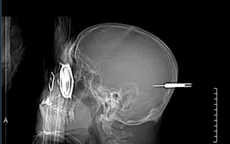

Cảnh báo hiểm họa từ súng hơi tự chế

VTV.vn - Bệnh viên Nhi đồng Cần Thơ vừa tiếp nhận bệnh nhi (13 tuổi, trú tại Kiên Giang) với chẩn đoán gãy hở độ IIIA xương bàn ngón cái chân trái còn dị vật do súng hơi tự chế.